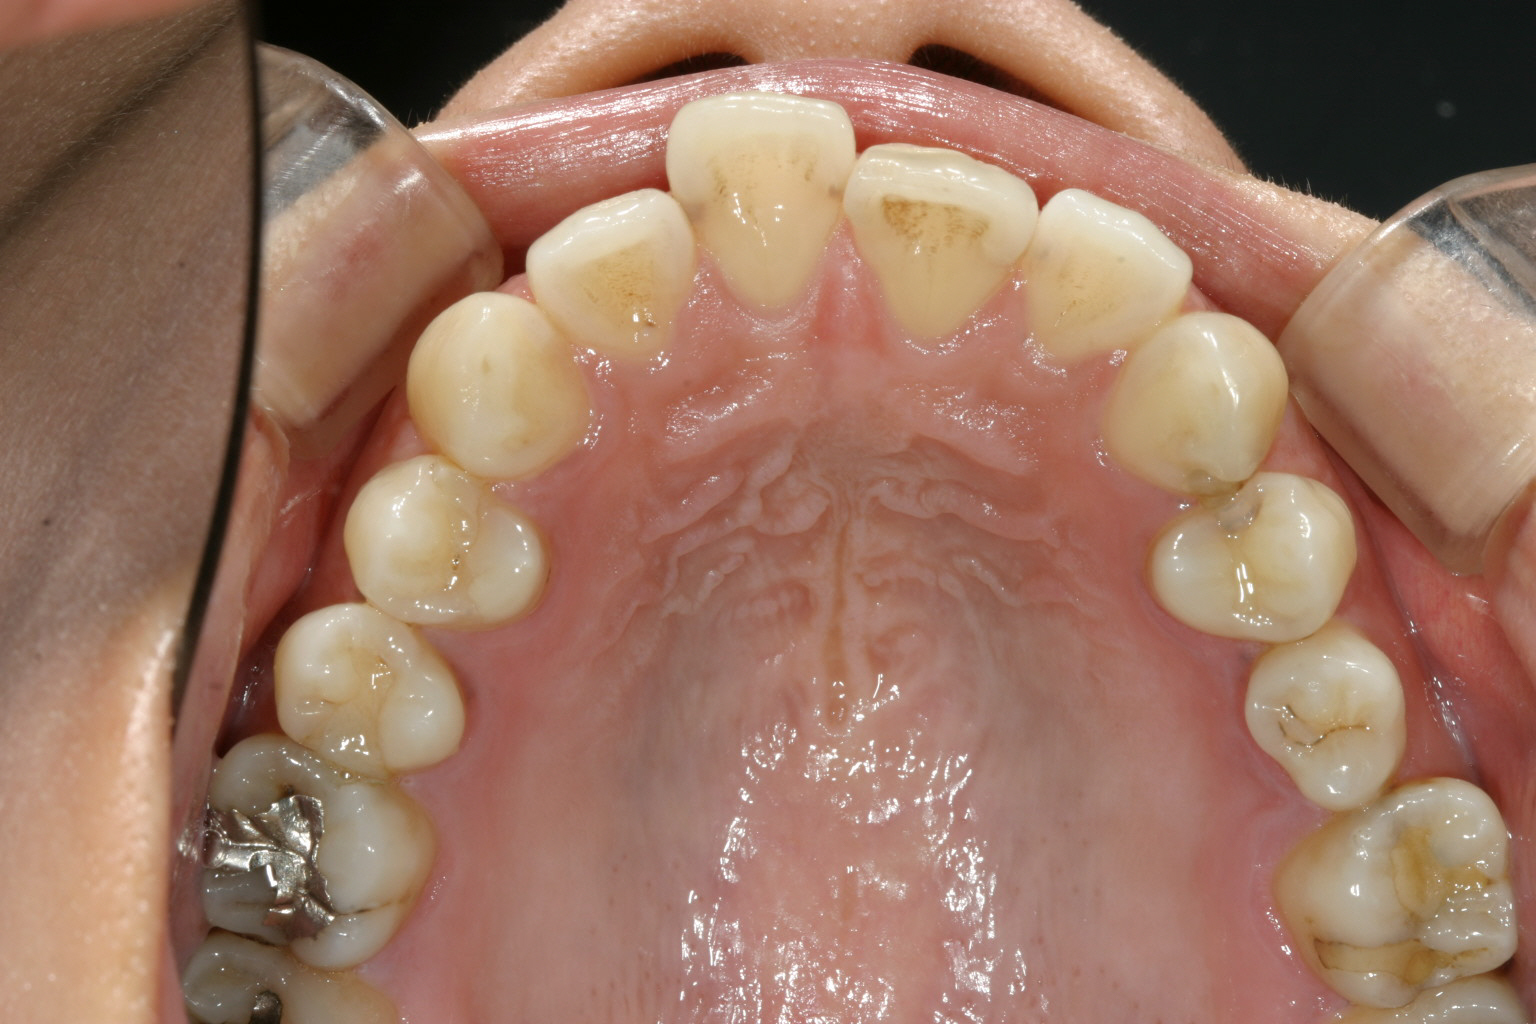

片前歯が飛び出し、又左上の5番目の歯が90度回転しているのが目立ちます。

下顎は少しの叢生が有ります。

前歯が少し歪んでいます。